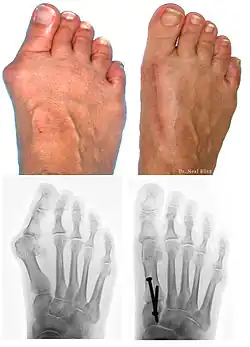

Treatment

Surgery

At present there are many different bunion surgeries for different effects. The age, health, lifestyle and activity level of the patient may also play a role in the choice of procedure.

Traditional bunion surgery can be performed under local, spinal or general anesthetic. A person who has undergone bunion surgery can expect a 6- to 8-week recovery period during which crutches are usually required to aid mobility. An orthopedic cast is much less common today as newer, more stable procedures and better forms of fixation (stabilizing the bone with screws and other hardware) are used. Hardware may even include absorbable pins that perform their function and are then broken down by the body over the course of months. After recovery long term stiffness or limited range of motion may occur in some patients. Visible or limited scarring may also occur for patients.